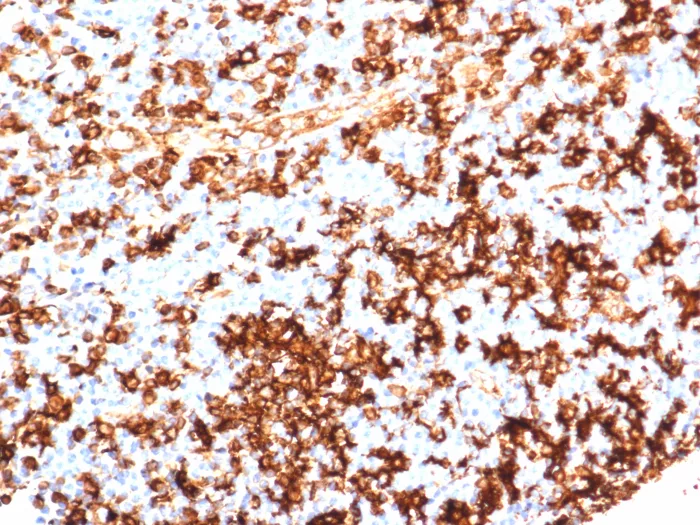

Formalin-fixed, paraffin-embedded human tonsil stained with HLA-DR Recombinant Rabbit Monoclonal Antibody (HLA-DRA/6839R). Inset: PBS instead of primary antibody; secondary only negative control.

This MAb reacts with the beta-chain of HLA-DR antigen, a member of MHC class II molecules. Â �It does not cross react with HLA-DP and HLA-DQ. The L243 antibody recognizes a different epitope than the HLA-DRA/6839R monoclonal antibody, and these antibodies do not cross-block binding to each other’s respective epitopes. HLA-DR is a heterodimeric cell surface glycoprotein comprised of a 36kDa alpha (heavy) chain and a 28kDa beta (light) chain. It is expressed on B-cells, activated T-cells, monocytes/macrophages, dendritic cells and other non-professional APCs. In conjunction with the CD3/TCR complex and CD4 molecules, HLA-DR is critical for efficient peptide presentation to CD4+ T cells. It is an excellent histiocytic marker in paraffin sections producing intense staining. True histiocytic neoplasms are similarly positive. HLA-DR antigens also occur on a variety of epithelial cells and their corresponding neoplastic counterparts.